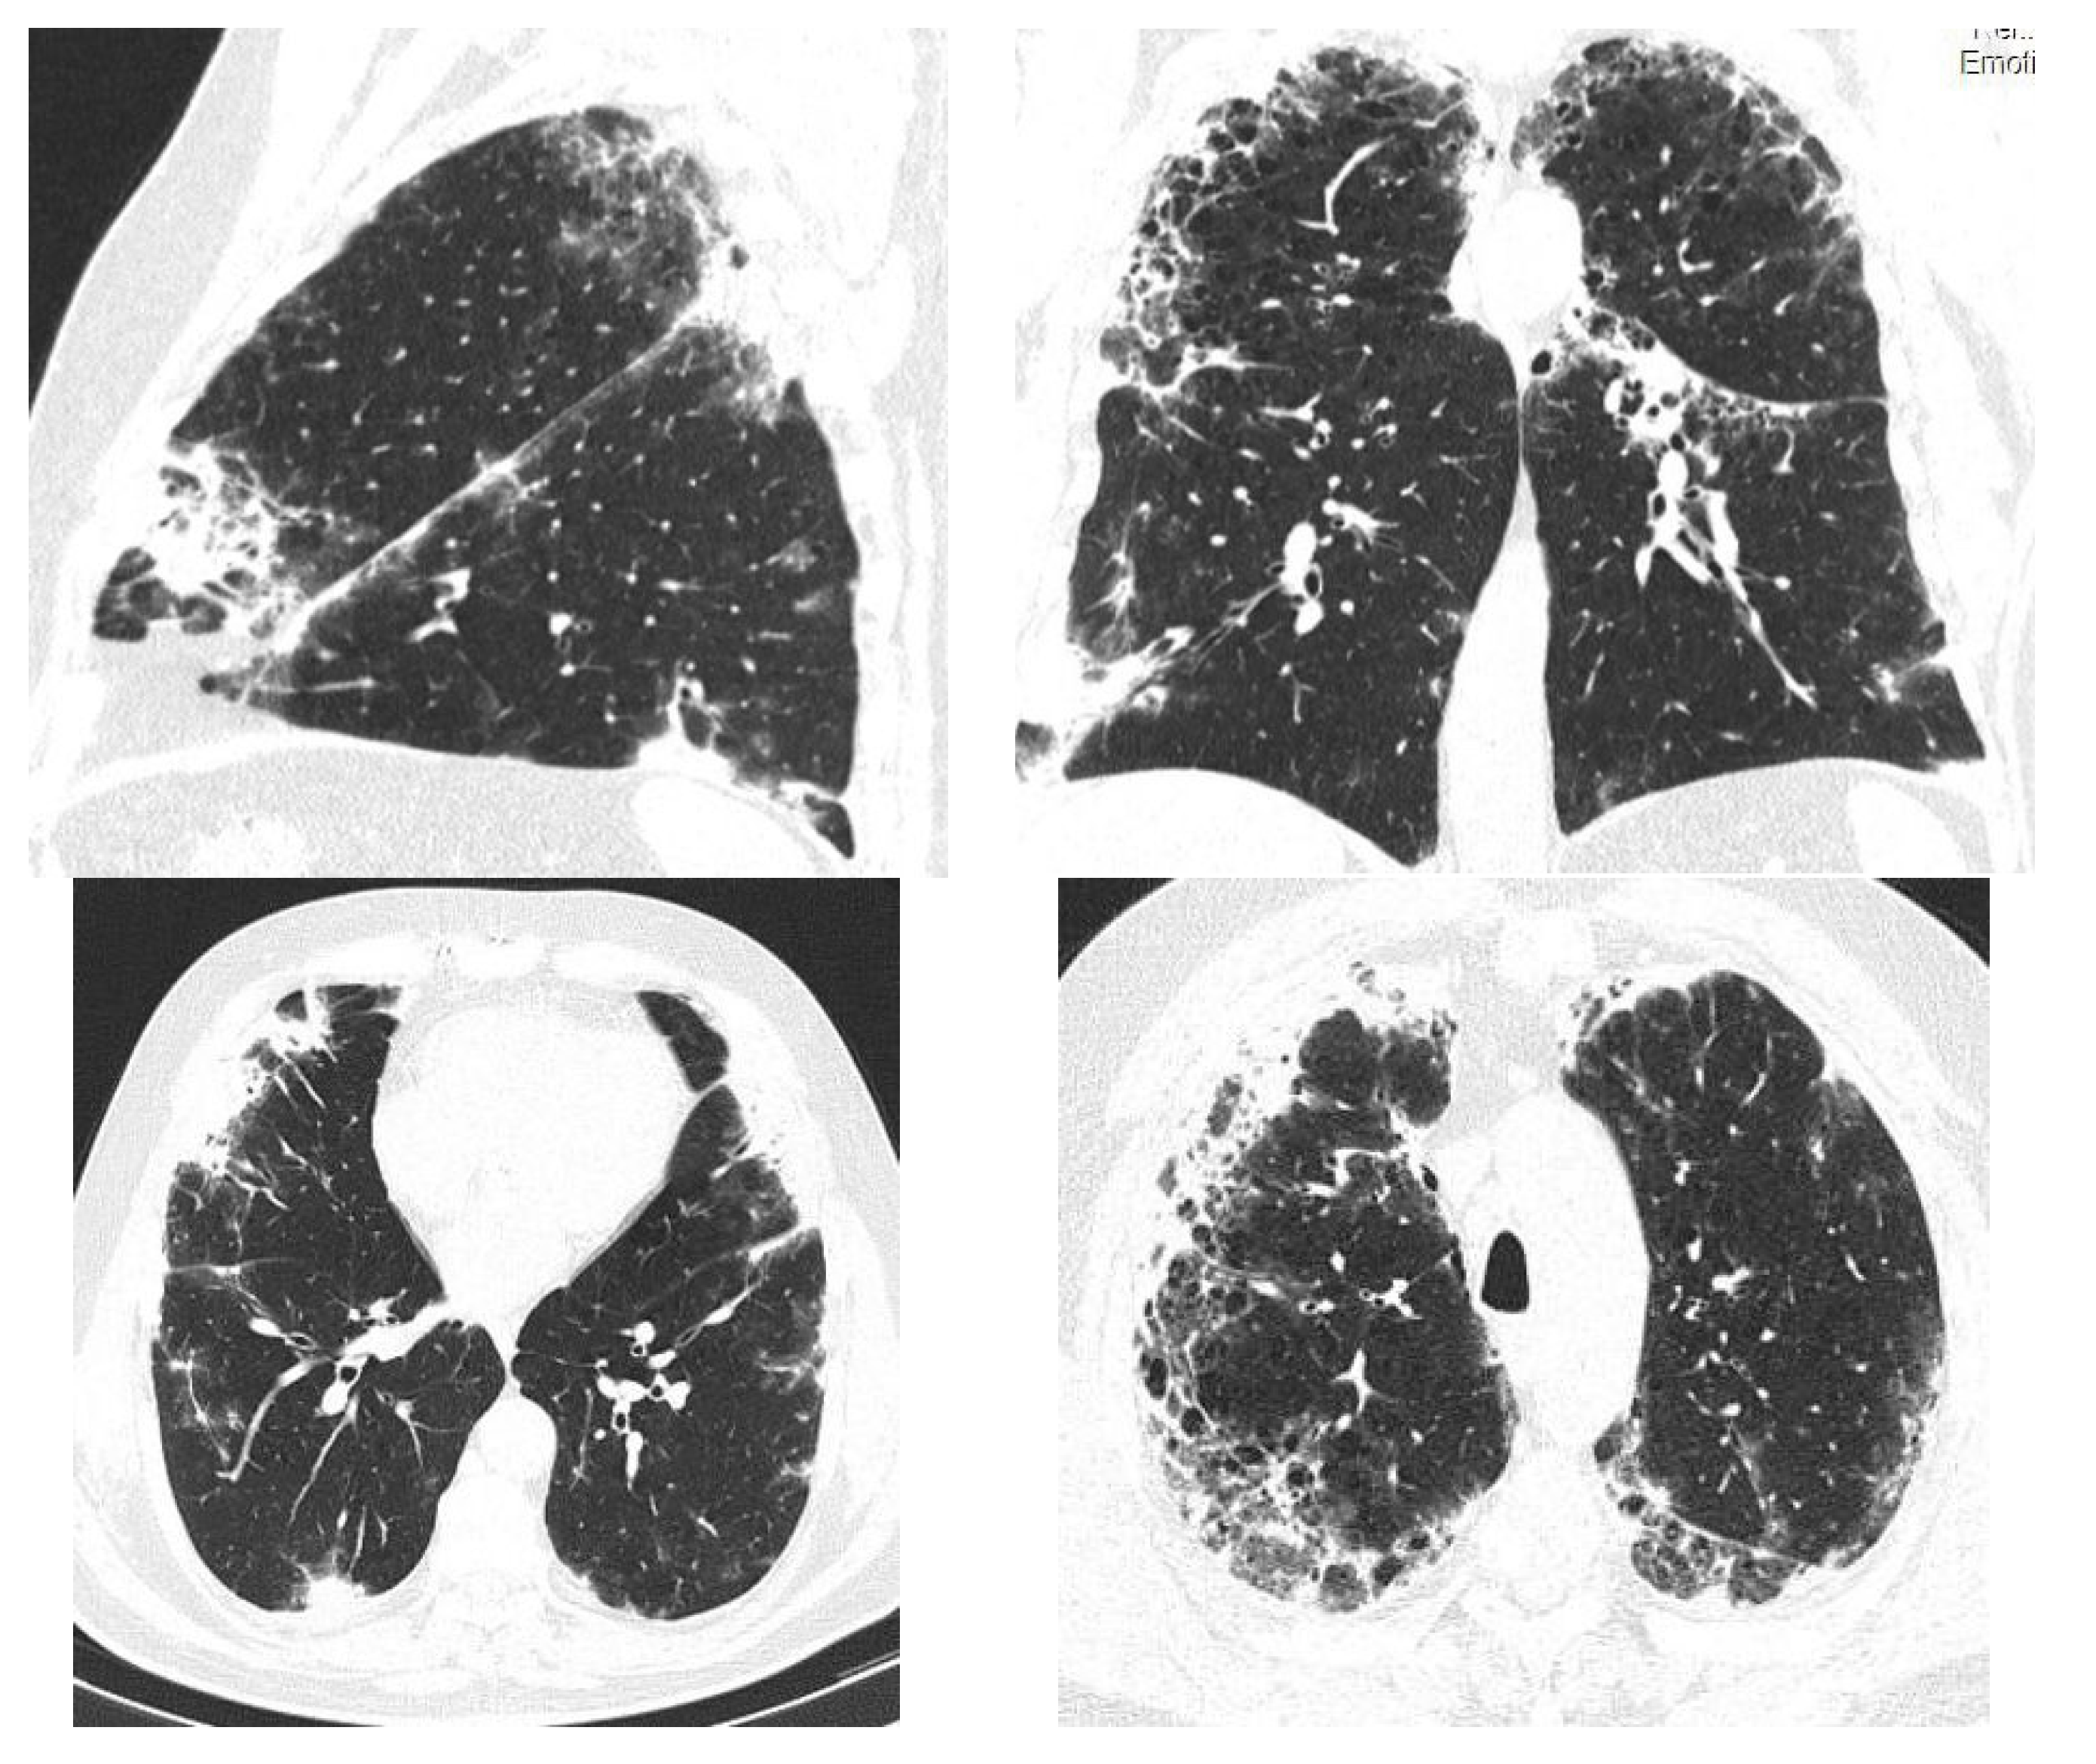

2.1. Case Presentation 1